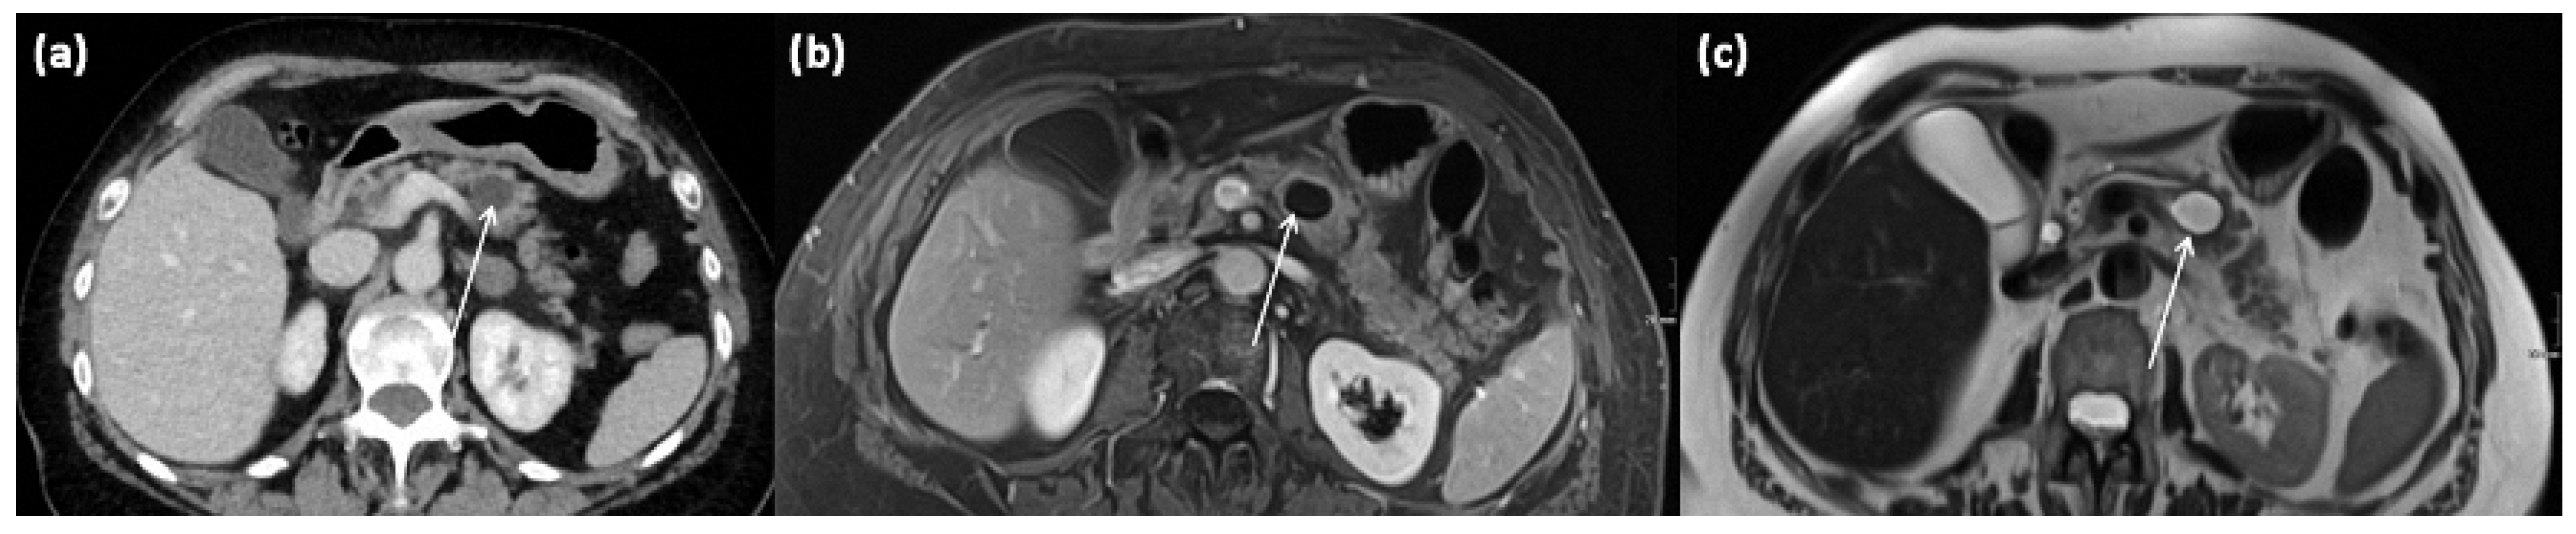

3.5. Intraductal Papillary Mucinous Neoplasms (IPMN)

3.5.1. Main Duct IPMN

3.5.2. Branch Duct IPMN